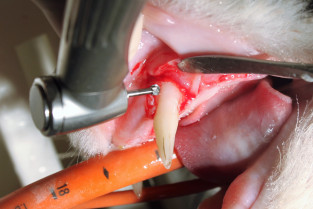

Ce cours modulaire permet d’acquérir des bases théoriques solides en odontostomatologie tout en assurant une formation pratique de qualité.

Les premiers jours visent à apprendre les compétences fondamentales à la mise en place d’un service en dentisterie :

• utilisation de l’instrumentation ;

• obtention de clichés radiographiques ad hoc ;

• réalisation d’extractions chirurgicales chez le Chien et le Chat.

Par la suite sont abordées :

• l’interprétation des images radiologiques ;

• les affections du parodonte et de la pulpe dentaire ;

• la gestion des stomatites ;

• les techniques de restauration dentaire et les premiers pas en orthodontie et chirurgie maxillo-faciale.